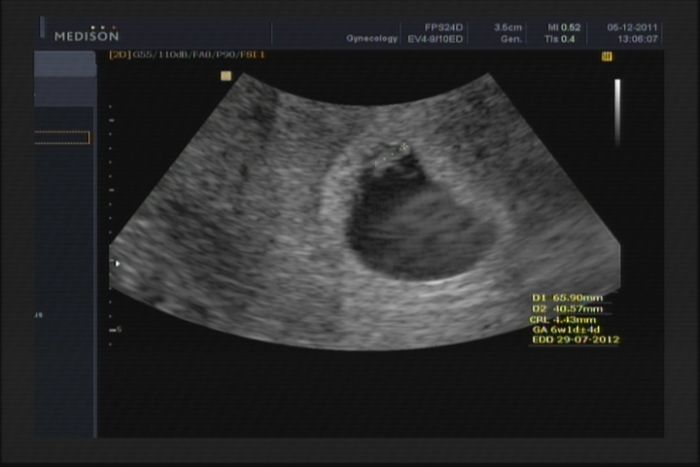

Ahoj holky, taky se musím pochlubit :-)...včera jsem měla být dle ms 6+6, dle ultrazvuku 6+1..

[60677] No je to ještě drobíneček :-)))..ale srdíčko blikalo jako o závod :-)